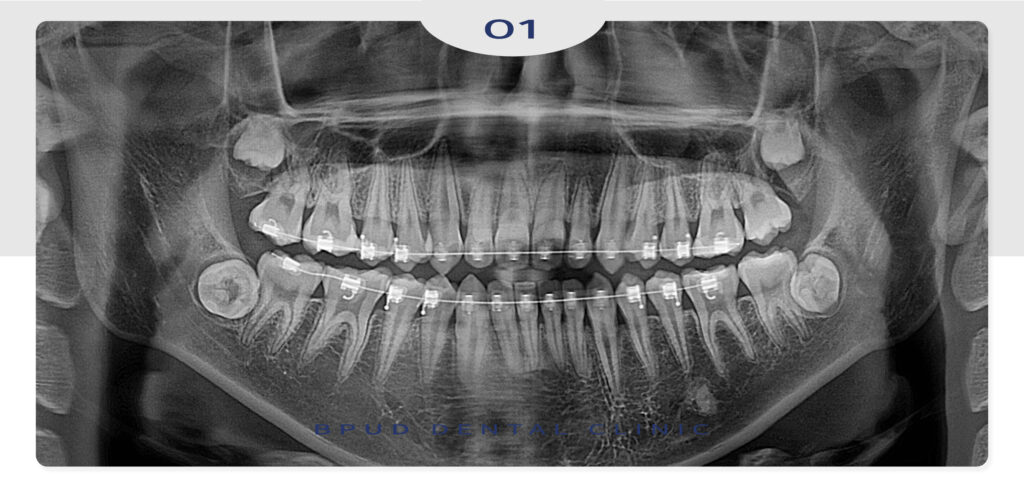

2025.08.04

치료의 마무리까지 18개월이 걸렸으며

생각보다 빠른 시간 내에 교정이 잘 마무리되어

만족해하셨습니다.